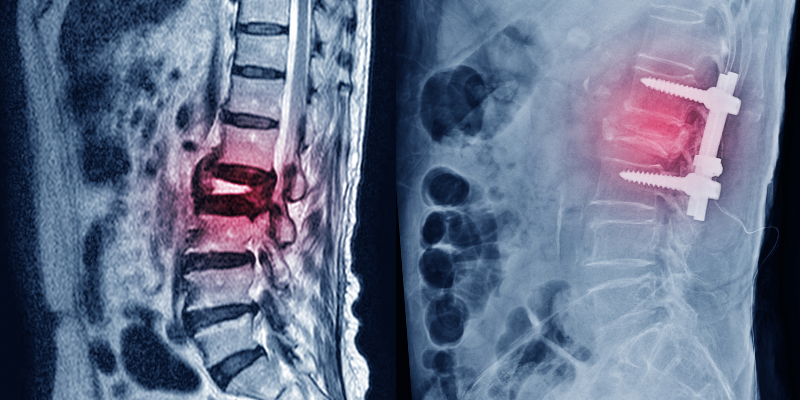

척추 유합술

척추 유합술을 시행하는 경우

• 분절성 요추 불안정성을 보이는 척추전방전위층

• 퇴행성 추간판 질환으로 척추관 협착,추간판 공간붕괴,측면 불안정증을 보이는 경우

• 척추 측만증

• 재발성 추간판 탈출과 연관된 기계적 요통

• 거대 추간판 중심성 탈출

• 후궁절제술 후 척추 후만 등 요추 변형

• 외상성 방출성 척추체 골절